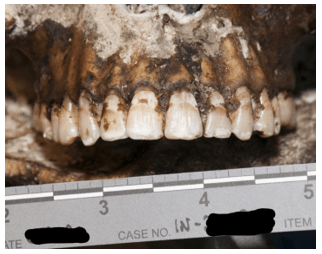

The second pathway by which we reach an undetermined manner is when extensive decomposition or other soft tissue loss (such as fire damage) interferes with our ability to determine a cause of death. Think of completely skeletal remains discovered in an abandoned building. Sometimes, indicators of potentially lethal injuries can still be identified – for example, a gunshot wound of the skull or knife marks on a rib. But, as the aphorism goes, “an absence of evidence isn’t necessarily evidence of absence” – a bullet or blade could be lethal while only striking soft tissue (especially in regions like the abdomen or neck). If we cannot rule out non-natural causes of death, the best choice for manner is “undetermined.”